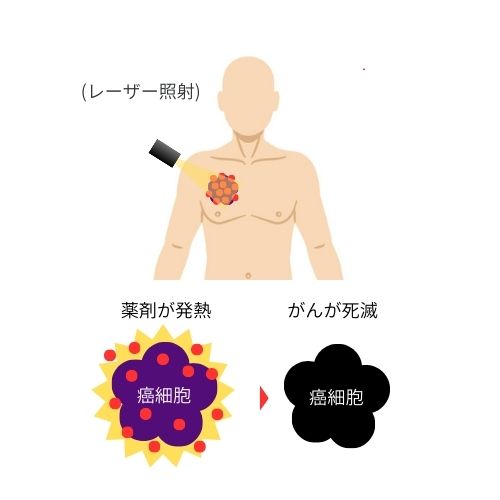

➃ 体表面照射

特定の波長を有したレーザーを体表面照射することで、がん細胞に集積した薬剤に反応させます。その結果、薬剤は発熱し、がん細胞を攻撃します。体表面照射を数回繰り返す事で、がん細胞を死滅させていきます。

図のように薬剤はレーザー光によって活性化し、活性酸素を生成してがん細胞を破壊します。

光を光感受性物質に当てると、その物質はエネルギーを放出し、この過程で活性酸素が生成されます。

これを「光化学反応」と呼びます。がん細胞は活性酸素に弱く、この活性酸素によって破壊されます。

一方、正常な細胞は活性酸素を無毒化する「オキシダーゼ」という酵素を持っているため、破壊されません。

これも、副作用が少ない理由の一つです。